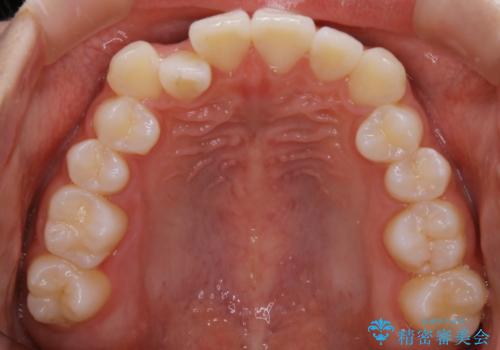

こちらの患者様の場合、上の前歯のガタつきが原因で口を閉じる際に上下の前歯の先端同士が先に当たってしまい、そこからさらに深く噛み込もうとすると下顎が前にずれていってしまうという、機能性の反対咬合であることが検査の結果わかりました。

そのため、まずは上顎の前歯のガタつきを改善していき、前歯が先に当たってしまうという症状を改善し噛み込む位置を後方の本来の位置に誘導する方法をとりました。